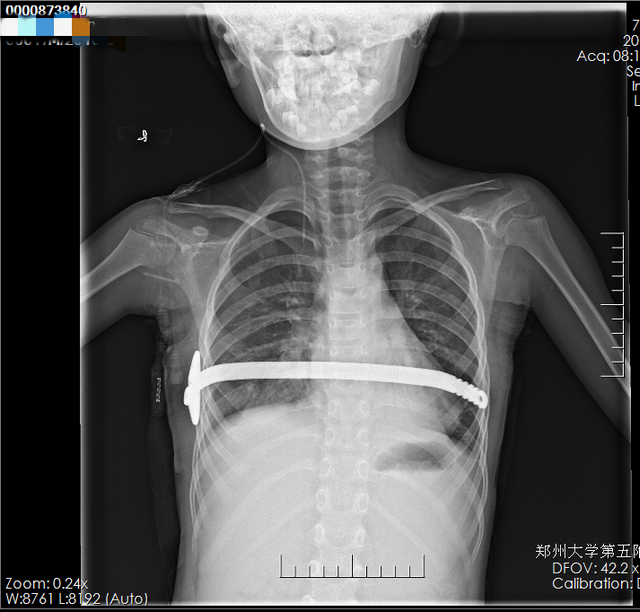

手术结束小许安返病房,家属惊奇的发现,孩子胸部的凹陷消失了,跟正常儿童一样。又经过几天的恢复,小许顺利康复出院,只要在术后的2年半到3年根据复查情况取出钢板即可。望着一家三人高高兴兴的样子,心胸外科的医务人员也露出了笑容。

▲ 术后X片检查